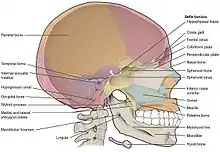

La base del cráneo está formada por el hueso etmoides, el esfenoides, las 2 porciones del hueso frontal, los 2 huesos temporales incluyendo su porción petrosa o peñasco y el hueso occipital. El conjunto se divide en tres compartimentos, la fosa craneal anterior, la fosa craneal media y la posterior. La fractura puede afectar a las tres fosas craneales, pero se localiza preferentemente en determinadas zonas que son puntos débiles de la estructura, entre ellos el techo de la órbita, la lámina cribosa del etmoides y el peñasco del hueso temporal.